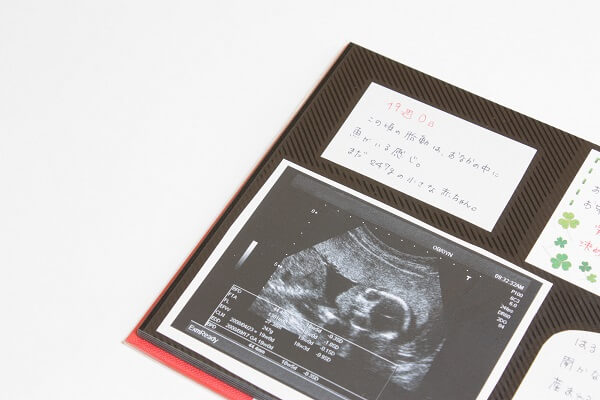

妊娠5ヶ月の最後の週である妊娠19週目。胎盤が完成し、ママの体調が安定して流産の可能性も低くなる安定期と呼ばれる時期ですが、無理をするのは禁物です。

妊娠19週目のママと赤ちゃんの様子についてご紹介します。

妊娠19週目ごろの赤ちゃんの大きさは、身長約25cm、体重約280gほどまでに成長しています。

胎盤が完成し、へその緒を通ってママから栄養や酸素をもらえるようになるため、より大きく成長していきます。

三頭身だった赤ちゃんは手足が伸びて四頭身に。皮下脂肪がついて、身体つきがふっくらしてきます。産毛や髪の毛も生え始めます。

顔つきもすっかり人らしくなっていて、3Dの超音波検査でかわいらしい目や鼻が確認できるようになってきます。

脳や内臓の各器官は日々発達しており、特に脳の発達は著しいものです。それにより、手足や指を器用に活発に動かせるようになるのです。